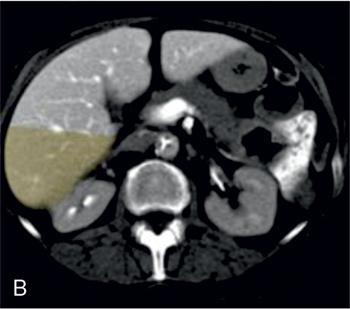

Ritu K. Kashikar, Shrinivas B. Desai Imaging is the mainstay of noninvasive diagnosis of the spectrum of abdominal pathologies or proving absence off thereof. Knowledge of normal anatomy and important normal variants is thus essential for the radiologist in order to avoid misinterpretation or erroneous diagnosis. This chapter highlights the normal anatomy of the hepatobiliary systems including the blood vessel and draining ducts and discusses relevant anatomical variants which may have important clinic implications. The liver is the largest abdominal organ, occupying the right upper abdominal quadrant and is in close approximation with the diaphragm, stomach and the gallbladder. It is largely covered by the costal cartilages. The liver is encapsulated by Glisson’s capsule which is a dense layer of connective tissue. It is covered by peritoneum, except in the regions of gallbladder fossa, fossa for inferior vena cava (IVC), and the bare area. The bare area is the posterocranial aspect of the liver, adjacent to the dorsal body wall, which is not covered by peritoneum. The liver has two surfaces, the convex diaphragmatic surface and a concave visceral surface. The slit in the hepatic hilum is called the porta hepatis and is penetrated by the right and left hepatic ducts (LHDs), hepatic artery and portal vein (PV). The distal portion of the lesser omentum is called the hepatoduodenal ligament and contains the common bile duct (CBD), hepatic artery, PV, nerves of liver and lymphatics. The liver has dual blood supply with hepatic artery providing 25% of hepatic blood and rest by portal vein (Fig. 9.2.1). Five ligaments connect the liver to the undersurface of the diaphragm. These include the falciform, the coronary and two lateral ligaments, all of which are peritoneal folds. The fifth ligament is a fibrous cord-like structure and represents the obliterated umbilical vein. The peritoneum invaginates into the liver parenchyma leading to formation of fissures. There are four normal fissures: fissures for the ligamentum teres, ligamentum venosum and gallbladder and the transverse fissure (Fig. 9.2.2). The liver is organized into microscopic functional units called lobules or acini. A central terminal hepatic venule surrounded by four to six terminal portal triads form a polygonal unit called the hepatic lobule. The terminal portal triad branches line the periphery of the unit. Between the terminal portal triads and the central hepatic venule the hepatocytes are arranged in one cell thick plates, surrounded by sinusoids. The blood flows from the terminal portal triad through sinusoids into terminal hepatic venule. Bile formed within the hepatocytes empties into terminal canaliculi which coalesce into the bile ducts (Fig. 9.2.3). This structure of the functional hepatic unit forms the basis of various functions of the liver. The normal relations of the liver are: The liver can be divided into right, left and caudate lobes. The right and left lobes are separated by the interlobular fissure and is oriented along a line passing through the gallbladder fossa inferiorly and the middle hepatic vein (MHV) superiorly (Fig. 9.2.4). This plane runs from the left of the IVC to the left of the gallbladder fossa and is a called the Cantlie’s line. Use of standardized, segmental anatomy is imperative because it facilitates communication and treatment planning. The segmental anatomy of liver is primarily based on vascular anatomy. The right lobe is divided into anterior and posterior sectors by of the right hepatic vein (RHV). The left lobe is divided into medial and lateraI sectors by an oblique plane connecting the left hepatic vein (LHV) and the falciform ligament. The liver is divided into upper and lower segments at the level of main portal vein (MPV) bifurcation (Fig. 9.2.5). Various systems are used in classification of liver anatomy. These are discussed in Table 9.2.1. The Couinaud’s system is the most commonly used and divides eight sections/segments which are discussed in details below (Table 9.2.2). 1. Segment 1 – Caudate lobe Bounded anteriorly and medially by the fissure for ligamentum venosum (Fig. 9.2.6). 2. Segment 2: Superior segment of the left lateral sector/section Bounded medially by falciform ligament and inferiorly by plane of MPV, also known as the posterior lateral sector (Bismuth, FCAT) (Fig. 9.2.7). 3. Segment 3: Inferior segment of left lateral sector/section Bounded medially by the falciform ligament and superiorly by the plane of the MPV bifurcation, also referred to as lateral anterior sector (Bismuth, FCAT) (Fig. 9.2.8). 4. Segment 4: Left medial sector/section Bounded laterally by falciform ligament and medially by Cantlie’s line (Fig. 9.2.9). 5. Segment 5: Inferior segment of the right anterior sector/section Bounded anteriorly by the gallbladder fossa and posteriorly by the plane of the RHV, superiorly bounded by the plane of MPV bifurcation (Fig. 9.2.10). 6. Segment 6: Inferior segment of the right posterior sector/section Bounded anteriorly by plane of the RHP and superiorly by the plane of the MPV bifurcation (Fig. 9.2.11). 7. Segment 7: Superior segment of the right posterior sector/section Bounded anteriorly by the plane of the RHV and inferiorly by the plane of the MPV bifurcation (Fig. 9.2.12). 8. Segment 8: Superior segment of the right anterior sector/section Bounded anteriorly by the plane of the gallbladder fossa and MHV, posteriorly bounded by the plane of the RHV and inferiorly by the plane of the MPV bifurcation (Fig. 9.2.13). Owing to its broad area of contact with the anterior abdominal wall, the liver is an ideal organ for evaluation with sonography. Ultrasound is commonly used for evaluation of size of the liver. On longitudinal scans obtained through the midhepatic line, if the liver measures 13 cm or less, it is normal in 93% of individuals (Fig. 9.2.14). The size of liver in various planes is discussed in chapter on normograms. When the area of contact between the liver and the anterior border of the right kidney, exceeds below two thirds of the kidney, the liver is considered as enlarged. The normal liver is homogeneous with fine echoes and appears evenly bright. The hepatic veins, PV and fissures interrupt the homogeneity of the liver parenchyma (Fig. 9.2.15). The parenchymal echogenicity may vary depending on the equipment, transducer and gain settings and should be judged by comparison with internal references like right renal cortex, body of the pancreas and PV walls. When compared with the adjacent normal right renal cortex the liver normally appears hyperechoic or isoechoic. The pancreas in a young individual is hypoechoic compared to the liver, and isoechoic in middle aged adults. As age progresses and fatty infiltration of the pancreas occurs, the pancreas appears hyperechoic to the liver. The liver is hypoechoic to the spleen. The normal liver reveals a density of 55–65 HU on nonenhanced scan and should appear homogenous with the exception of hypodensity in the regions of vessels and fissures. The liver parenchymal enhancement is minimal the arterial phase, with increase in density by only approximately 10 HU. This phase is usually to access vascular anatomy and to detect neovascular enhancing lesion like HCC, metastasis. Considering the fact that 75% of heptic venous supply is from the PV, the normal hepatic parenchyma shows maximum enhancement in the portal venous phase. During the venous/delayed phase the hepatic attenuation starts falling (Fig. 9.2.16). The hepatic fissures appear as linear fat containing structures. All the four fissures are well identifies on CT (Figs. 9.2.17–9.2.20). Normal liver should demonstrate uniform T1 signal similar or isointense to the paraspinal muscles and slightly hyper intense to the spleen. No signal drop should be seen on in or opposite phase. On T2W1 images liver appears slightly hyperintense to paraspinal muscles, isointense to pancreas and hypointense to spleen (Fig. 9.2.21). Following administration of extracellular contrast agents the normal liver parenchyma enhances on PV phase similar to that seen on CT. The arterial phase is preserved to determining vascular anatomy, variants and tumoural enhancement. Gadoxetic acid (Eovist) and gadobenate dimeglumine (MultiHance) are hepatobiliary agents showing excretion by the liver. In the case of gadoxetic acid, hepatic excretion is ~50%, which allows imaging in the hepatobiliary phase at ~20 minutes following injection. Gadobenate has only 3%–5% biliary excretion with hepatobiliary phase at approximately 40 minutes (Fig. 9.2.22). This property makes these agents useful in detection of nonhepatocyte containing lesions which appear hypointense to background liver on hepatobiliary phase. Hepatic anatomic variants are relatively common and represent normal interindividual variation of liver morphology. Normal Anatomic Variants Anatomic anomalies Accessory and pseudofissures may be seen in the liver. True accessory fissures result from infolding of the peritoneum usually along the undersurface of the liver and are rare. The inferior accessory fissure is the commonest accessory fissure and divides the posterior segment of the right hepatic lobe into lateral and medial portions. Diaphragmatic slips may cause indentation over the liver surface and are not commonly seen on imaging (Fig. 9.2.23). Leftward extension of the lateral segment of the left hepatic lobe appearing as a crescentic density that wraps around the spleen is referred to as sliver of liver. The left lobe of the liver may exhibit various forms: leaf like; spatular; truncated pyramid/wedge shaped; and a bifid appearance (Fig. 9.2.24). Elongated left lobe may be mimic splenomegaly, perisplenic hypoechoic collections or less commonly tumours. Imaging clues to diagnosis are establishing contiguity with liver and visualization of parenchymal vessels coursing through. The portion of the liver that extends medially from the right lobe between the IVC and fissure for ligamentum venosum is called the caudate lobe. The caudate lobe is divided inferiorly into a lateral caudate process and a medial papillary process. The medial papillary process projects medially towards the pancreatic head and has applied importance (Fig. 9.2.25). Riedel’s lobe is a tongue-like projection from the anterior aspect of the right lobe and the most common accessory lobe of the liver. It is seen most frequently in asthenic women. The reported prevalence of RL, ranges from 3.3% to 14.5% and the prevalence is higher in women than in men. It can be 20 cm or more in length and may extend up to the iliac fossa. It is usually asymptomatic and is discovered incidentally (Fig. 9.2.26). Accessory liver lobes are defined as a supernumerary lobe of normal hepatic parenchyma in continuity with the liver. This is a rare entity and usually occurs as a result of congenital ectopic hepatic tissue, although rarely may occur as a result of trauma or surgery. Various systems are proposed for classification of ALL. Another method of classification has been proposed based on biliary drainage and presence or absence of capsule. Accessory lobes can be readily diagnosed and characterized on CT or magnetic resonance imaging (MRI) done for related or unrelated conditions. CT shows the lesion as a soft–tissue density mass attached to the liver and isodense to the organ. The portal/hepatic venous branches can be seen coursing through it, in contiguity with the liver (Fig. 9.2.27). The coeliac axis trifurcates into common hepatic, splenic and left gastric arteries at the level of T12–L1. The common hepatic artery becomes the proper hepatic artery after origin of the gastro-duodenal artery. The hepatic artery proper ascends anterior to the PV and medial to the CBD and divides in to right and left hepatic artery (LHA). Occasionally the middle hepatic (segment 4) artery arises from hepatic artery proper. The hepatic artery appears as a tubular hypoechoic structure and shows antegrade flow on Doppler (Fig. 9.2.28). Normally the resistive index is low ranging between 0.55 and 0.7. The hepatic artery, its anatomy, branches, course, calibre are best evaluated on arterial phase of dynamic CT (Fig. 9.2.29). This is also the preferred modality prior to hepatobiliary surgical planning. Contrast-enhanced MRI also shows the above details but spatial resolution is lower. Road map of the arterial vascularity of the donor and recipient is a prerequisite for transplant surgery and complex hepatobiliary surgery. Detailed hepatic arterial anatomy and its variations have its significance in liver surgeries and interventional hepatic procedures, relative to the hepatic lobe involved. A classification method was described by Michel et al. in 1955, and is discussed in Table 9.2.3 (Fig. 9.2.30). I: standard anatomy ~60% (range 55%–61%) II: replaced LHA ∼7.5% (range 3%–10%) III: replaced RHA ~10% (range 8%–11 %) IV: replaced RHA and LHA ~1% V: accessory LHA from LGA ~10% (range 8%–11%) VI: accessory RHA from SMA ~5% (range 1.5%–7%) VII: accessory RHA and LHA ~1% VIII: accessory RHA and LHA and replaced LHA or RHA ~2.5% IX: CHA replaced to SMA ~3% (range 2%–4.5%) X: CHA replaced to LGA ~0.5% Other unclassified variants are: The two most common variants are the replaced right hepatic artery (RHA) arising from the SMA (Fig. 9.2.31) and replaced LHA arising from the left gastric artery (Figs. 9.2.32–9.2.34). Segment 4 artery – Middle hepatic artery (MHA) The middle hepatic artery usually arises from the LHA, it may, however, arise from the RHA (Fig. 9.2.35). The knowledge regarding origin of MHA is imperative in transplant surgery. The MHA can arise from RHA in Patients with replaced LHA. In patients with replaced RHA, the MHA arises from LHA (Fig. 9.2.36). Because of the considerable variability of hepatic arterial anatomy, assessment of this anatomy is crucial in the preoperative evaluation of potential living liver donors. Relevance of donor and recipient arterial anatomy is discussed in details in chapter on liver transplant. The relationship between the arterial variant and tumour is important to establish prior to major surgeries. Injuries to aberrant hepatic vessels and secondary ischaemic biliary strictures can be avoided. A replaced RHA has a more posterior course and long length. This variant may be advantageous in patients undergoing right lobar resection. However, there is greater propensity of involvement of replaced RHA by pancreatic head. The radiologist must be vigilant in reporting this variant (Fig. 9.2.37). Accessory RHA can, however, be sacrificed even if encased by neoplasm. An accessory LHA needs to be ligated separately in surgeries where blood supply in the porta hepatis is occluded. Replaced LHA from LGA maybe injured in case of surgeries at the level of hiatus. Hence this variant should be informed to surgeon in patients undergoing gastric surgeries. Preoperative mapping of the hepatic arterial anatomy prior to placement of intraarterial chemotherapy pumps is essential because it helps in deciding whether the candidate is suitable for the procedure and also if technical modifications are needed. The intraarterial infusion pump should be placed in the dominant hepatic artery as proximal as possible, but beyond GDA origin. Inpatients with standard anatomy, the pump is usually placed in the hepatic artery prior just after GDA origin. The location of pump can be modified in patients with variant anatomy, based on origin of GDA and dominant hepatic vessel. The PV is the main vessel in the portal venous system and drains blood from the gastrointestinal tract and spleen to the liver.